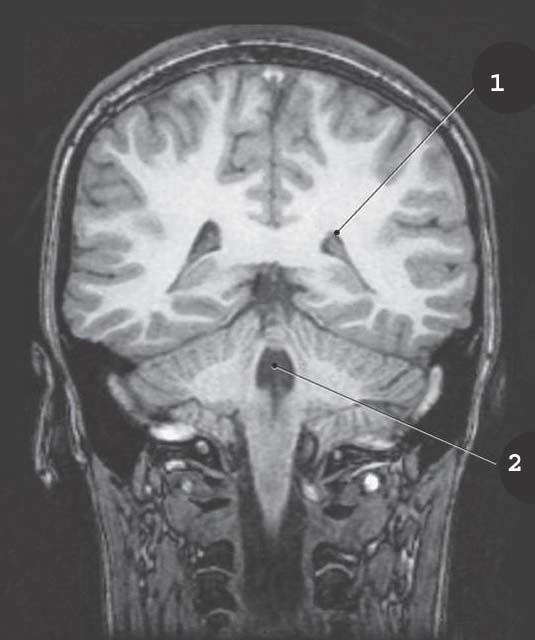

1

Lateral Vetnricle

2

4th ventricle